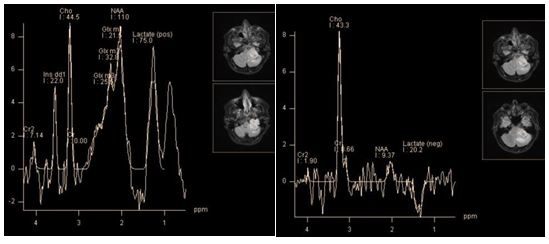

Spectroscopy of pyogenic brain abscess and empyema demonstrate presence of specific metabolites such as succinate, acetate, alanine, valine, leucine, isoleucine, lactate and lipids, which makes it possible to differentiate them from other brain cystic lesions (Figure 5 & 6) High levels of lactate, acetate and succinate can be explained by increased glycolysis and fermentation of microorganisms. Such amino acids, as valine and leucine are the final product of proteolysis by enzymes released by neutrophils in pus.14 Neurons in abscesses are absent, so peaks of NAA and Cr should not be detected. The presence of these peaks can be explained only by misplaced voxels, or its contamination from adjacent parenchyma. Also, an acetate peak, which is close to NAA resonance frequency (Ac - 1.95 ppm, NAA - 2.01 ppm), can be erroneously attributed to the latter. Cho is also absent in the abscess cavity, since the necrotic core lacks membranes.

Figure 5 Chronic pyogenic abscess. PRESS, TE 135 ms. The spectra from the abscess cavity (a) show inverted peaks of lactate (1.31 ppm), amino acids (isoleucine, leucine and valine - 0.96 - 1.01 ppm), and the abscess wall(b), shows an inverted peak of lactate and considerable reduction of N-acetylaspartate.

Figure 6 Meningitis. Spectra obtained from Lateral sulcus area near the small subdural empyema, PRESS, TE 135 ms (a) Map of succinate concentration. The peak of succinate 2.4 ppm can be seen (a), and its maximum concentration is localized in the sulcus (b).

TBC abscesses are characterized by dominant lipid peaks and the presence of Cho. The presence of cytolytic amino acids have not been observed.15

The results of spectroscopy in differential diagnosis between purulent abscesses and necrotic tumors are not always unambiguous, but the presence of the abovementioned amino acid peaks undoubtedly testifies to the abscess (Figure 5 & 7). Note that in chronic abscesses after drug treatment peaks of amino acids cannot be detected.16